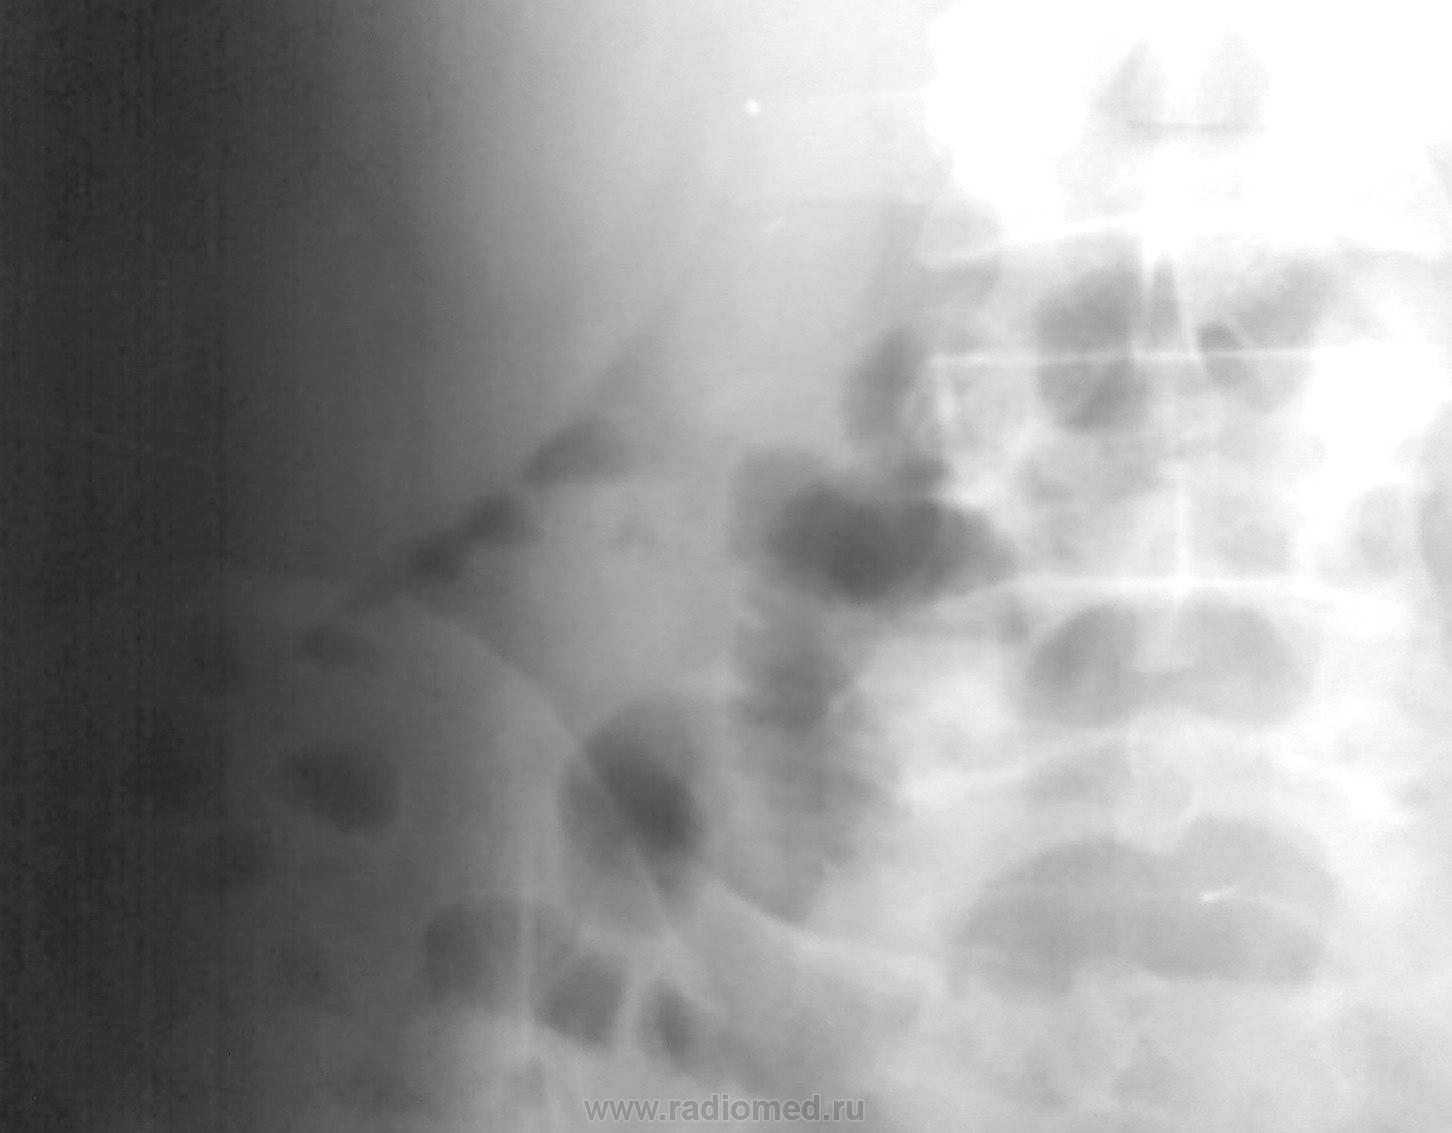

Для начала - направление из приемного "острый аппендицит", а вот и снимочек...что скажете?

Ответ, насколько понял, известен. Ввяжусь, а там посмотримsmiley. Такую фрагментарную пневматизацию, с менисковидными малыми уровнями жидкости, расценил бы как проявление динамической кишечной непроходимости.

Андрей Юрьевич, все так, но между тем Вы прекрастно знаете, что, направление больного для исследование по поводу подозрения на аппендицит - чрезвычайно редкое явление. Недооценка рентгенологического исследования в диагностике аппендицита вряд ли может быть оправдана достаточной надежностью только клинических данных. Так что вопрос открыт - могут ли мелкие менископодобные уровни в правой половине толстой кишки и "дежурная" тонкокишечная арка в мезо/гипогастрии справа косвенно свидетельствовать в пользу острого аппендицита?

Раздута терминальная петля подвздошной кишки, далее много воды, мало воздуха - цепочка мелких уровней - "жемчуг", такие же меленькие уровни в проекции селезеночного угла. Но газа в поперечно-ободочной и нисходящей крайне мало. Вывод: имеется проблема в илеоцекальной области. Аппендицит/аднексит вероятны. Рентгенкартина функциональных нарушений при воспалительном заболевании с местным перитонитом, недавний процесс.

И опять изолированая тонкокишечная петля в подвздошной области справа, да  уровни в печеночном углу, естестственно. Картина соответственна тяжести состояния, я так понимаю, в отличие от "просто аппендицита", который демонстрировался вначале)))

Видите ли, Виктор Григорьевич, у меня на этот счет своего мнения нет, целиком полагаюсь на мнение Щербатенко и Бересневой (Склиф). Они указывали, что нет специфической р-картины о.аппендицита. В этом случае я тоже написал: р-картина кишечной непроходимости, вероятнее всего динамической.